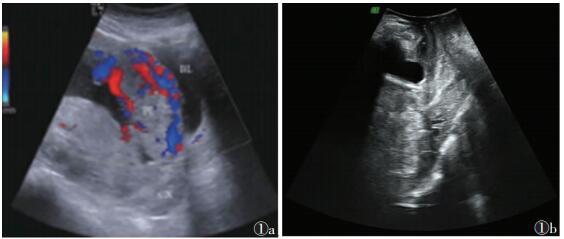

2 结果 2.1 诊断结果86例经产后病理证实为凶险型前置胎盘者67例。产前单纯经腹超声的诊断符合率为82.09%(55/67),误诊4例,漏诊8例;产前经腹联合经会阴超声检查的诊断符合率为97.01%(65/67),漏诊2例,差异有统计学意义(χ2=7.976,P=0.005)。经腹联合经会阴超声声像图见图 1。

| 图 1 女,29岁 图 1a 经腹彩色多普勒超声示胎盘前壁内及覆盖部位的血管分布增多 图 1b 经会阴彩色多普勒超声示胎盘完全前置,子宫下段膨隆,胎盘后方肌层低回声带消失 |